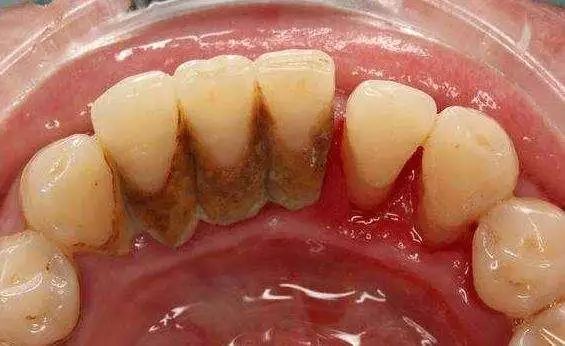

-超声波全口洁牙-

牙龈与牙根面之间不是紧密附着,而是存在一条0.5—2mm的浅沟,称龈沟。龈沟内易积存食物碎屑,附着菌斑,而且龈沟是难以彻底清洁的区域。

一般在刷牙之后的半小时内即会有新的菌斑形成,久而久之即成为牙结石,这些细菌会引起牙龈炎、牙周炎、出血、口臭,最终引起牙齿松动,甚至脱落。

而洗牙,是借由各种器械来去除这些附着于齿颈与牙龈沟之间的牙结石及牙菌斑,可以减轻牙龈炎、牙周炎的炎症状况。